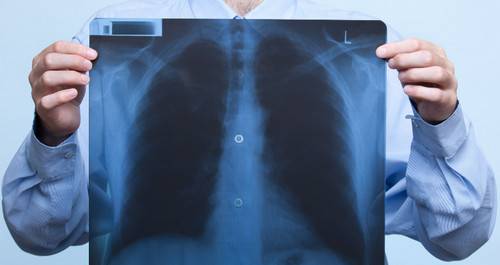

- Сделать рентген (к сожалению, пока не в каждой больнице есть аппаратура для обследования лежачих больных). Скопившаяся в лёгких жидкость на плёнке даст тени и уменьшение прозрачности, но «картинка» будет неотличима от других лёгочных болезней – например, бронхопневмонии.

- рентгенография органов грудной клетки;

- Рентген. С помощью него можно обнаружить кровяной застой в малом круге и увеличение правых сердечных отделов.